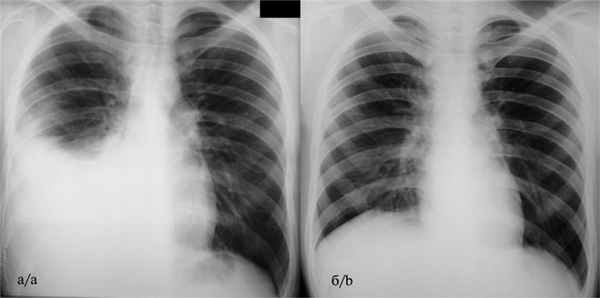

Рентгенологически I стадия эмпиемы характеризуется синдромом гидроторакса с формированием классической косовосходящей линии Соколова—Эллиса—Дамуазо (рис. 1, а). Рис. 1. Обзорная рентгенограмма органов грудной клетки больной А. до (а — правосторонний гидроторакс с формированием линии Соколова—Эллиса—Дамуазо) и через 1 мес (б — явления правостороннего гидроторакса полностью купированы без остаточных изменений) после видеоторакоскопической плеврэктомии.

На этой стадии туберкулезной эмпиемы мы отдаем предпочтение ранней ВТС-санации полости эмпиемы, что позволяет наиболее эффективно и быстро ликвидировать симптомы интоксикации и уменьшить риск развития хронической эмпиемы. Во время этой операции выполняют следующие этапы: 1) эвакуация серозно-гнойного экссудата; 2) вскрытие отдельных затеков и осумкований; 3) удаление наложений фибрина с висцеральной и костальной плевры; 4) частичную париетальную плеврэктомию в области наиболее выраженных воспалительных изменений для гистологической верификации процесса и ускорения резорбции экссудата из плевральной полости; 5) дренирование полости эмпиемы для дальнейшего удаления экссудата, местной антибактериальной терапии и противотуберкулезной химиотерапии.

Преимущества операции туберкулезной эмпиемы плевры в I стадии: морфологическая верификация диагноза в сомнительных случаях; выявление микобактерии туберкулеза (МБТ) и определение чувствительности к противотуберкулезным препаратам; ускорение рассасывания экссудата, быстрое купирование клинических проявлений, уменьшение сроков лечения; профилактика формирования грубых плевральных рубцов с потерей функции легкого (см. рис. 1, б).